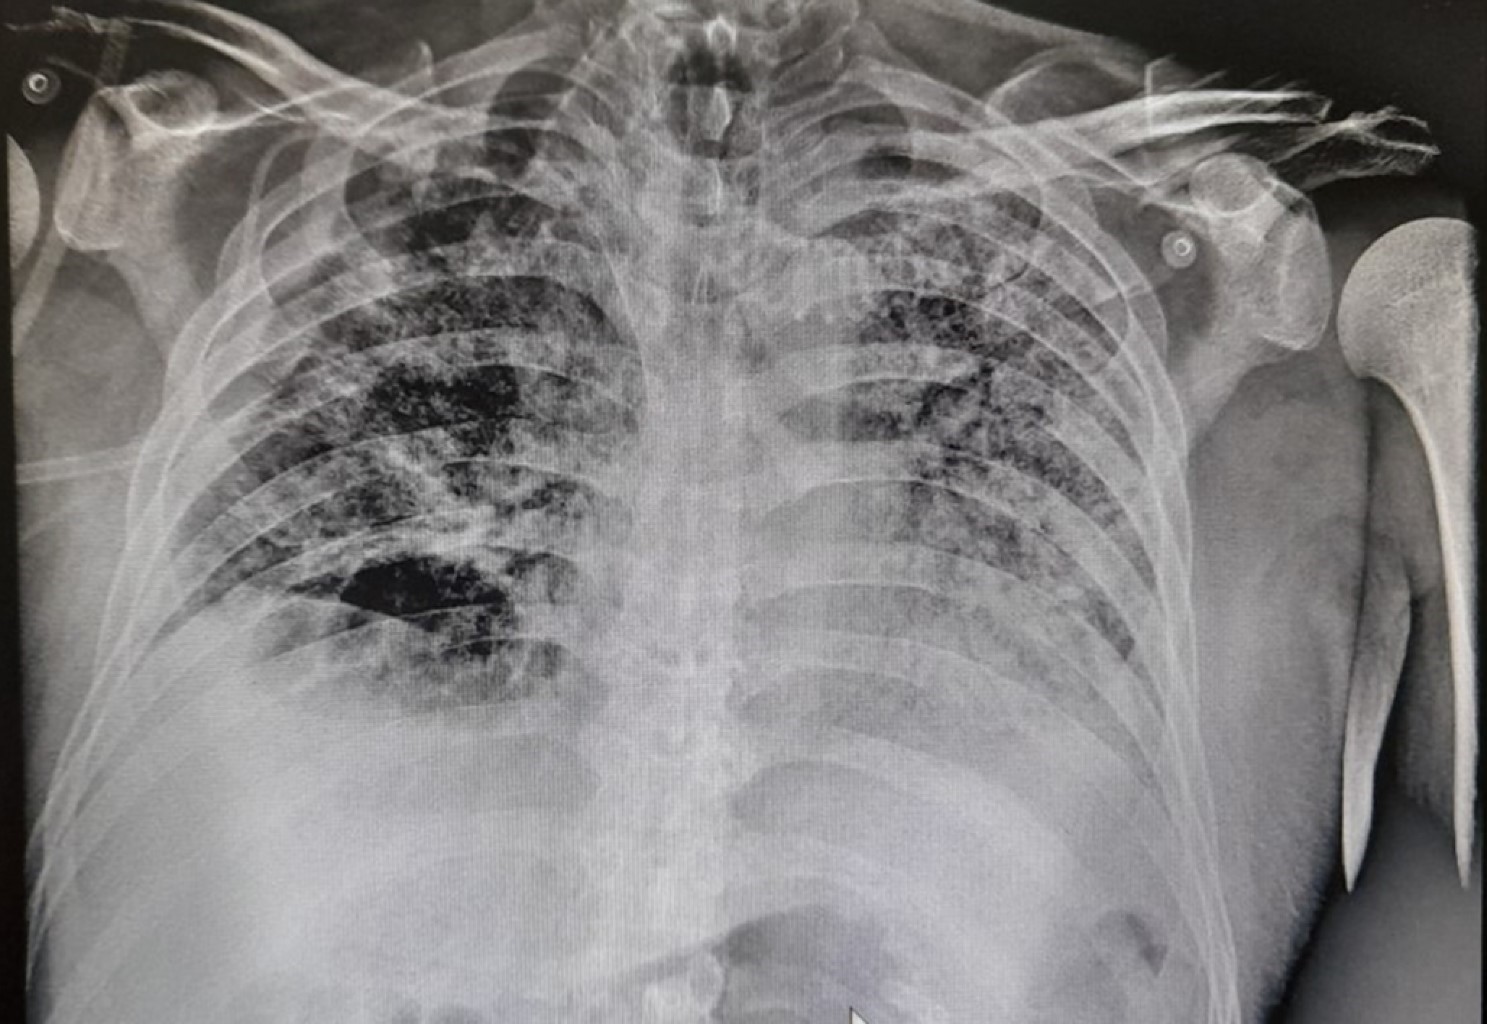

Se decide colocar sonda endopleural en quinto espacio intercostal en su intersección con la línea axilar media derecha obteniendo 200 mL de material serohemático, se conecta a succión continua, se verifica colocación de sonda endopleural con control radiográfico posterior (Figura 3). Se solicita valoración por el servicio cirugía de tórax, quien indica manejo conservador con seguimiento a través de estudios de imagen. Se retira la sonda endopleural a los 10 días de colocada, corroborando expansión pulmonar (Figura 4). Se logra el retiro de la ventilación a los 68 días de iniciado el cuadro y 58 días de ventilación mecánica tolerando de manera adecuada, siendo egresado a sala general para continuar con su manejo.

Figura 4